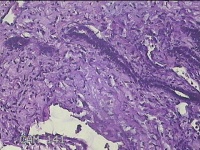

右侧卵巢囊肿

性别

女

年龄

36岁

临床诊断

一般病史

发现双侧附件囊肿1年。

标本名称

大体所见

灰白暗红色囊壁样组织2.5x2x0.3cm一块,表面光滑,部分已切开,囊内容物已流失,囊壁厚0.2cm。

考虑:子宫内膜异位囊肿。